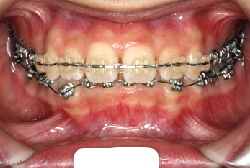

凸凹な歯並びのことを叢生といいます。矯正歯科に来院する患者様の主訴の中で、最も多いのが「配列の凸凹を真っ直ぐにしたい」というものです。歯の大きさと顎の大きさの調和がとれていないことが原因です。

凸凹を主体としたケースの場合、当院の平均治療期間は18ヶ月ですので、このケースは少し長めに経過しました。理由の一つは凸凹の程度がかなり重症だったと言うことですが、もう一つは、右下第2大臼歯が45度くらい前傾していたため、それを整直化させるために時間を要したと考えています。いずれにしても最終結果は大変よい状態と思います。

治療前は並びが乱れて見た目が悪いというのはもちろん問題ですが、歯科医学的に一番困るのは噛み合わせが悪いという点です。上下の犬歯(3番目の歯)は、上下的に離れた位置にあるため接触することができません。つまり歯としては存在していても、歯としては機能していないということです。